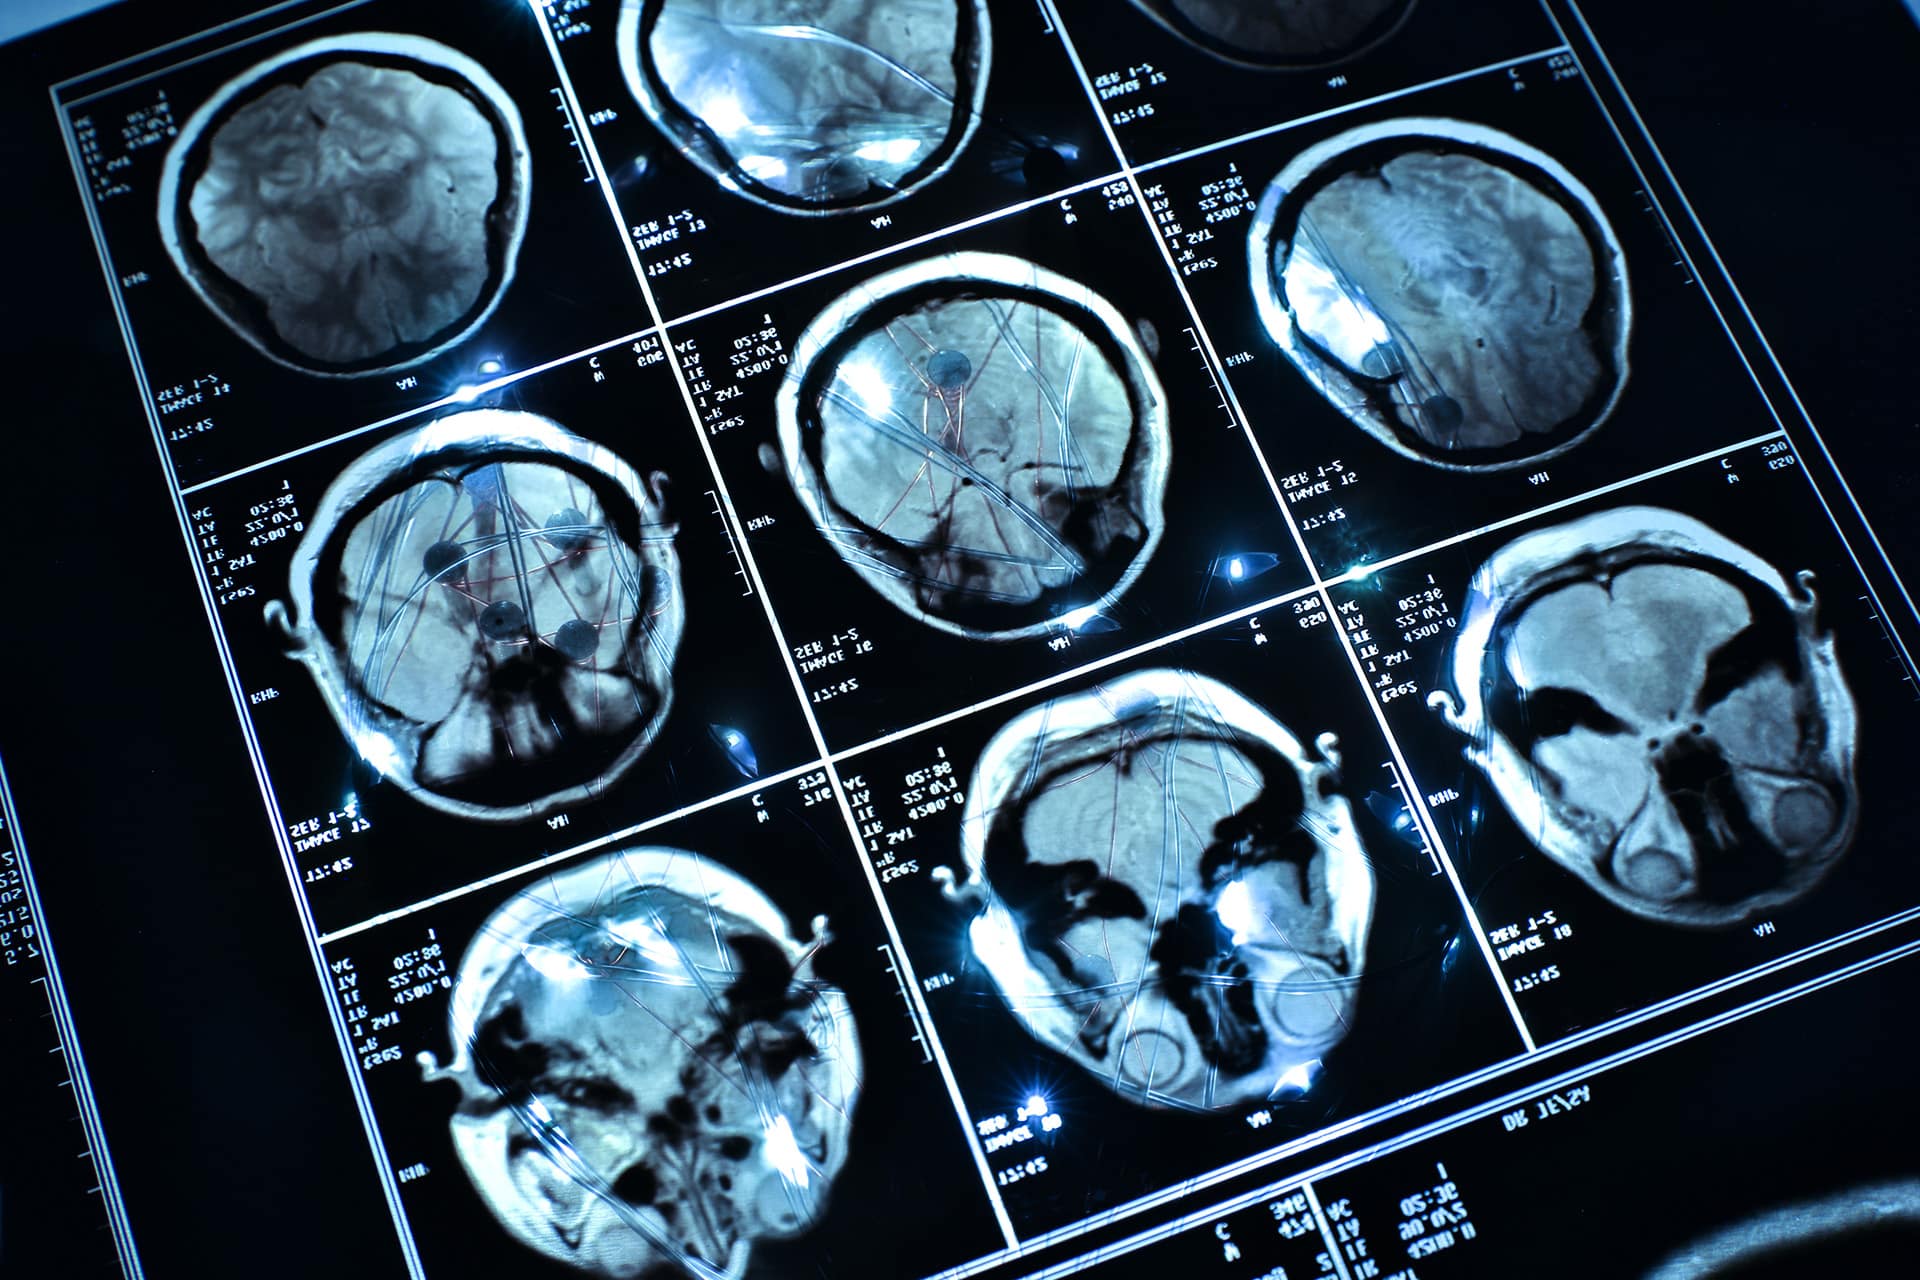

Los investigadores, que combinaron análisis de escáneres cerebrales humanos con experimentos en animales, descubrieron que el dolor persistente provoca cambios progresivos en el hipocampo. Estos cambios determinan si los pacientes desarrollarán depresión con el tiempo o mantendrán su resiliencia emocional.

Mediante el análisis de escáneres cerebrales de grandes cohortes poblacionales, incluyendo datos del Biobanco del Reino Unido, los científicos observaron diferencias significativas:

-Las personas con dolor crónico sin depresión presentaban un volumen del hipocampo ligeramente mayor y una mayor actividad en esta región, acompañada de un mejor rendimiento en tareas de aprendizaje y memoria. Esto sugiere que el cerebro inicia una respuesta compensatoria ante el estrés del dolor.

-Por el contrario, quienes padecían tanto dolor crónico como depresión mostraban un volumen del hipocampo reducido, actividad alterada y peor rendimiento cognitivo.